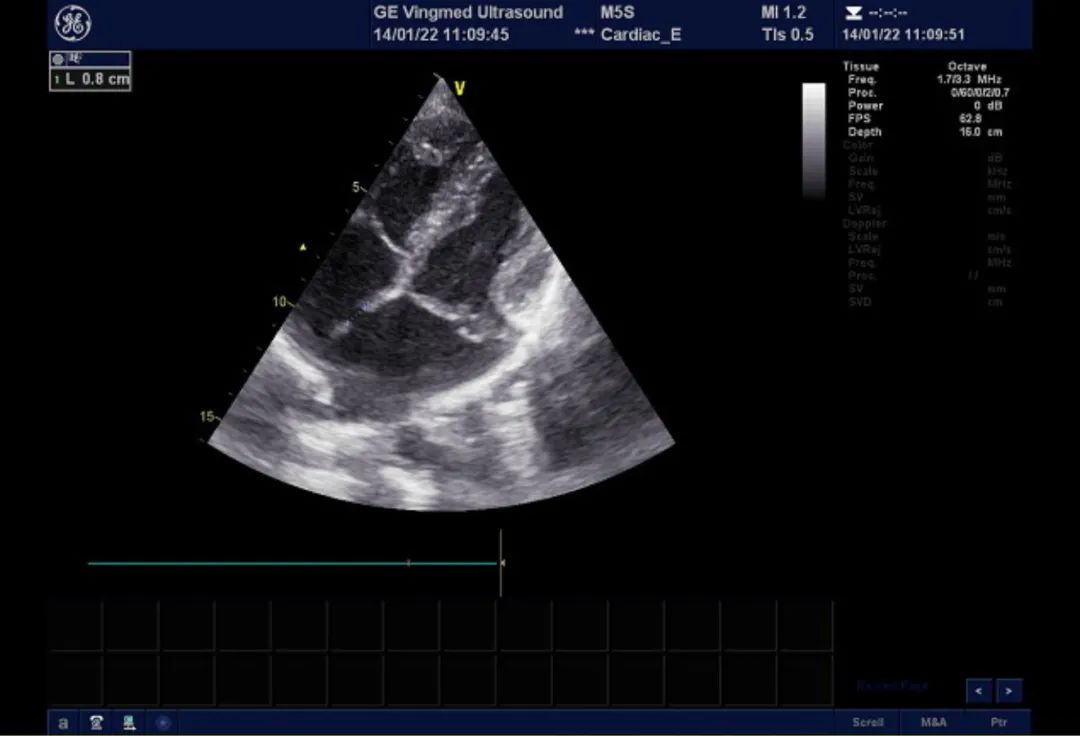

心脏超声:AO:26mm, IVSd: 8mm, LVDd:44mm, FS:43%,HR:84BPM LA:39mm, LVPWd:8mm, LVDs:25mm, LVEF:74%,RV:36mm M型、2-DE:左房饱满,大小约45*55mm,左室大小正常范围,右心增大,右房大小约44*51mm,升主动脉不宽,主波明显,重搏波清晰,主瓣清晰,启闭无殊;二尖瓣增粗、增强,后叶收缩期凸向左房,P2区为主。室壁不厚,室间隔与左室后壁逆向运动。肺动脉主干内径21mm。静息状态下各切面未见室壁节段性运动异常。房间隔可见两处回声中段,孔1位于近十字交叉处,宽约11mm,十字交叉残端不明显。孔2位于房间隔中段,宽约9mm。三尖瓣瓣环内径约38mm。超声诊断先天性心脏病,房间隔缺损(继发孔型,双孔型考虑),二尖瓣后叶脱垂伴关闭不全(P2区为主,中重度)。

二尖瓣后叶脱垂,大量返流

双孔型房缺,分别为1cm及8mm大